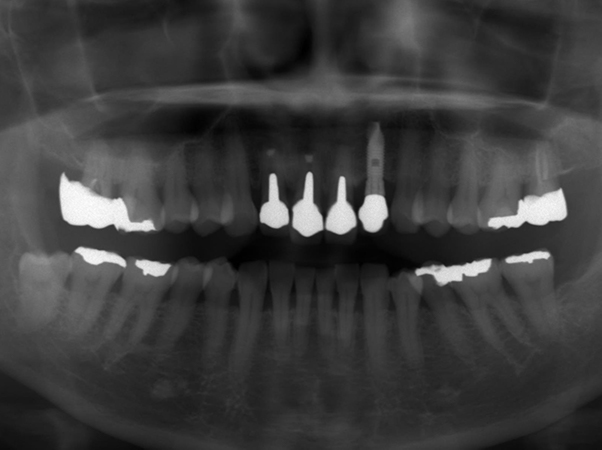

初診時パノラマレントゲン写真

デンタルレントゲン写真

右上1番と2番、左上1番の根の先には大きな病変(レントゲン上で黒く写っている部分)が確認できました。右上1番と2番に関しては、15年ほど前に歯根端切除を行っているとのことより、再手術を行うと現状よりもさらに歯根が短くなってしまい、歯の揺れが大きくなることが予想されました。

右上1番と2番、左上1番の根の先には大きな病変(レントゲン上で黒く写っている部分)が確認できました。右上1番と2番に関しては、15年ほど前に歯根端切除を行っているとのことより、再手術を行うと現状よりもさらに歯根が短くなってしまい、歯の揺れが大きくなることが予想されました。